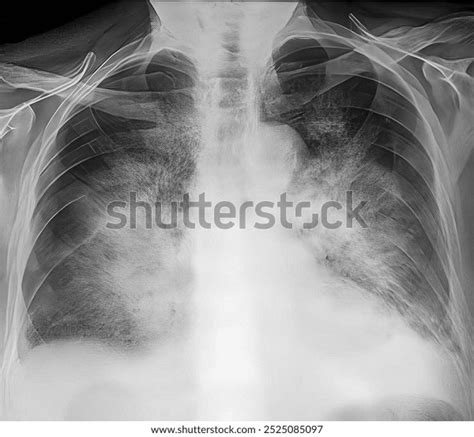

So, first things first, what exactly is this ‘batwing appearance’ we’re talking about when it comes to X-rays? Imagine you’re looking at an X-ray image of someone’s lungs. Sometimes, certain conditions can cause the lung tissue in the central part of the chest to look denser or whiter than usual. This whiter, denser area often spreads outwards from the center towards the edges of the lungs, resembling the outstretched wings of a bat. That’s where the name comes from! It’s a descriptive term that radiologists use to quickly convey a specific pattern they see on the image. This pattern isn’t a disease in itself, but rather a visual clue that something might be going on in those central lung zones. It’s crucial to remember that this is an interpretation of an image, and a doctor will always consider it alongside your symptoms, medical history, and other tests to make a proper diagnosis. Think of it as a signpost pointing towards potential issues, not the final destination itself. The distribution of this opacity is key; it’s typically bilateral (affecting both lungs) and most pronounced in the perihilar regions – that’s the area around the hilum, where the major bronchi and blood vessels enter and leave the lungs. This symmetrical, central pattern is what makes it so distinctive and earns it the ‘batwing’ moniker. It’s a visual shorthand that helps medical professionals communicate and understand findings efficiently. Without this descriptive term, radiologists might have to use a much longer, more complex description to convey the same pattern, which could lead to misinterpretation or delays in diagnosis. So, while it might sound spooky, it’s actually a very useful descriptive tool that aids in the diagnostic process, helping to narrow down the possibilities and guide further investigations.

Let’s circle back to pulmonary edema , as it’s such a common reason for that batwing sign on an X-ray. When we talk about pulmonary edema, we’re essentially talking about fluid overload in the lungs. Your lungs are designed to have tiny air sacs, called alveoli, where oxygen enters your bloodstream. In pulmonary edema, these alveoli get filled with fluid instead of air. This makes it much harder for oxygen to get into your blood, which can leave you feeling short of breath and uncomfortable. The batwing appearance specifically highlights the central distribution of this fluid. Why central? Well, the blood vessels that bring blood to and from the lungs converge at the hilum, which is the central part of the lung. When there’s increased pressure in these vessels, often due to the heart not pumping effectively (congestive heart failure is a big one here, guys), fluid tends to leak out into the surrounding lung tissue in these central areas first. This fluid accumulation looks white on an X-ray because fluid is denser than air and absorbs more of the X-ray beam. This density creates the characteristic white shadowing that radiologists describe as the batwing pattern. It’s like a spotlight shining on the core of the lungs, showing where the problem is concentrated. So, the batwing sign is a powerful visual indicator that fluid is accumulating in the lungs, and it strongly suggests a cardiac origin, though other causes exist. Recognizing this pattern helps doctors quickly prioritize potential diagnoses and initiate appropriate management. Treatment for pulmonary edema usually involves addressing the underlying cause – for instance, using medications to help the heart pump better or to remove excess fluid from the body (diuretics). Improving breathing might involve oxygen therapy. The key is prompt recognition, and the batwing X-ray appearance is a significant clue that alerts the medical team to this urgent situation. It’s a classic radiological sign that has been used for decades to guide the diagnosis and management of patients with suspected heart failure or other causes of fluid overload in the lungs. Without this visual cue, diagnosing such conditions might take longer, potentially delaying critical treatment. Therefore, its importance in clinical practice cannot be overstated.